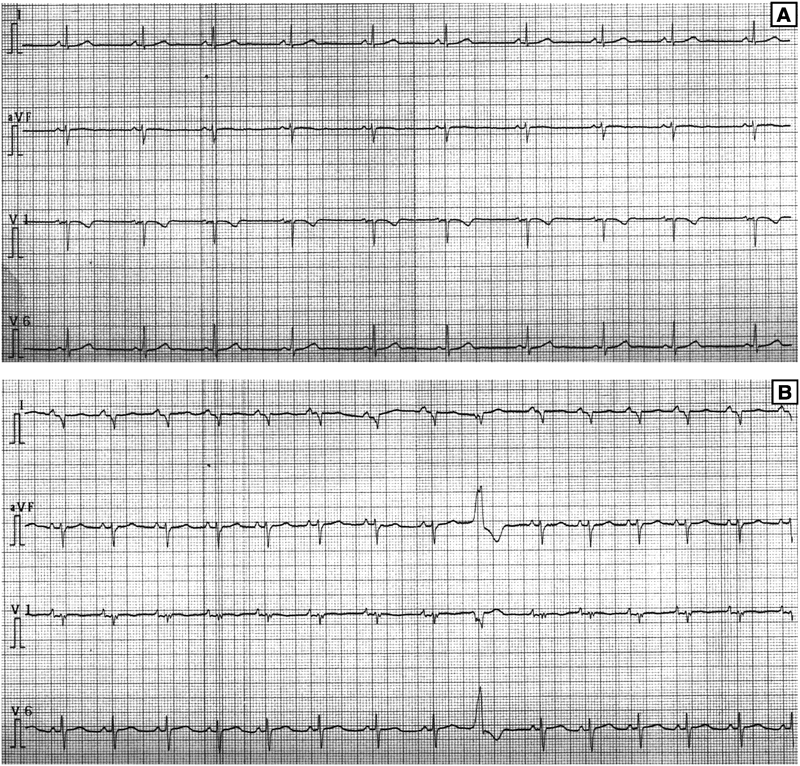

生来健康であった9歳男児.学校心臓病検診で心電図異常を指摘された.学校検診の心電図では6歳時には異常を認めなかったが,9歳3か月での検査ではI誘導でQSパターン,心室性期外収縮(PVC)を認めた(Fig. 1).成長発達で異常を認めず,突然死や心筋症等の家族歴はなかった.学校心臓病検診受診の際には動悸,胸痛,易疲労感などの自覚症状は認められなかったが,9歳5か月頃には倦怠感と動悸を自覚するようになっていた.他院を受診時には心胸郭比67%と心拡大を認め,BNP1474 pg/mLと高値であった.心不全治療および不整脈治療として利尿薬,PDEIII阻害薬,β遮断薬,アミオダロンを開始されたうえで,PVCに対するカテーテル焼灼術目的に当院に転院となった.

Fig. 1 Electrocardiogram at annual school check up

A: 6 years old, B: 9 years old. A; Electrocardiogram showed normal pattern. B; QS pattern in lead I, and premature ventricular contraction were noted.